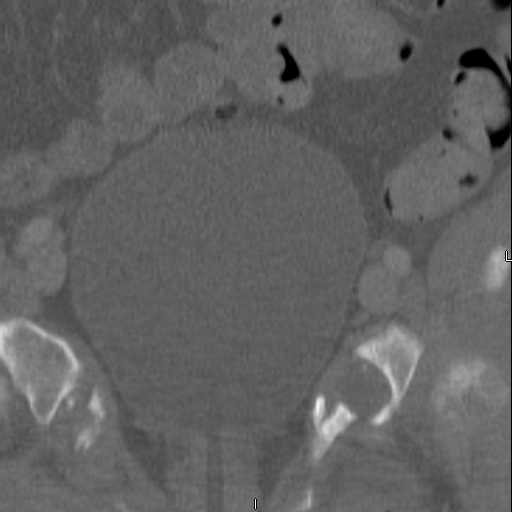

Here are a recent patient’s example slides...

54 yo Female Fell c/o Pain

Initial Films

?Instability on Exam - Limited by Pain

NonOp Initial Mgmt

3 Months After Fall

Continued Pain & Immobility

(+) Instability to Compressive Manual Exam

Pelvic CT Scan - 3 Months After Fall

Sacral Injuries

Ramus Fractures